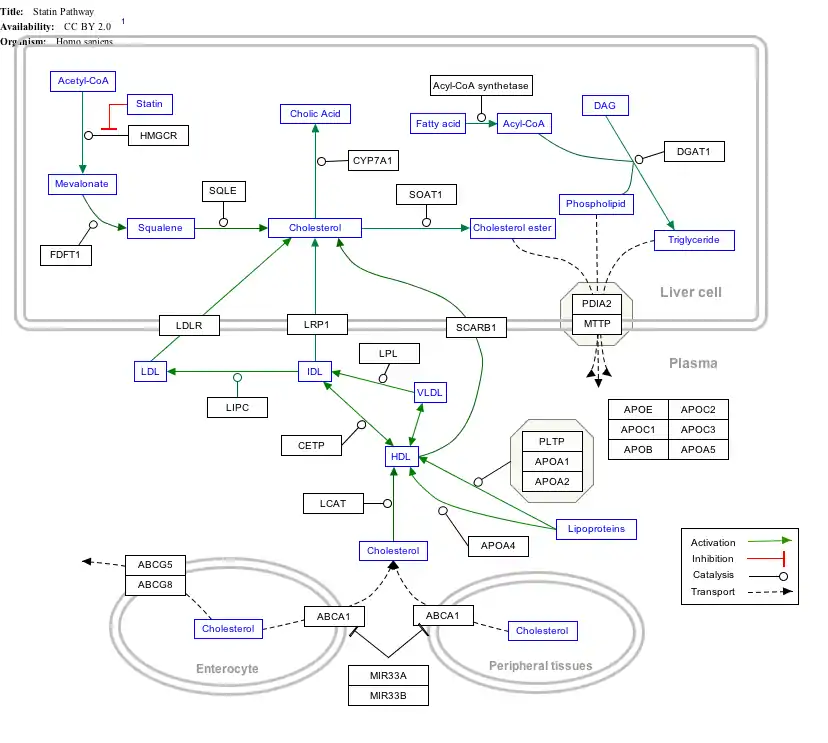

Interactive pathway map

Click on genes, proteins and metabolites below to link to respective articles. [§ 1]

- ↑ The interactive pathway map can be edited at WikiPathways: "Statin_Pathway_WP430".